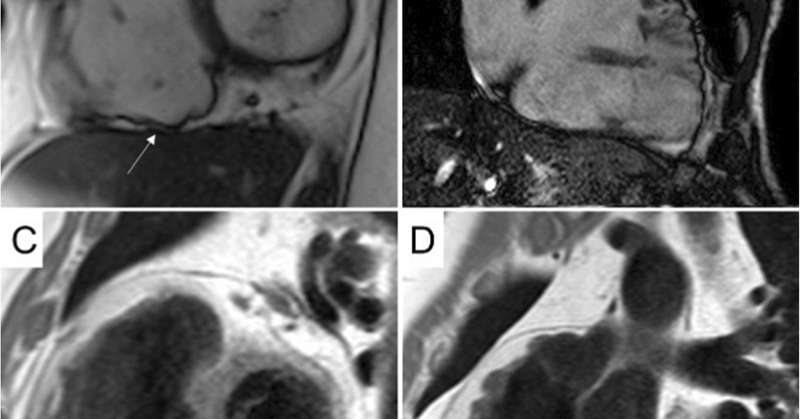

Just published open access in @Europace: #ecg characteristics of premature ventricular beats help identify patterns at-risk of underlying LV scar in #athletes #sportscardiology #cmr @EuropaceEiC

https://t.co/nnf0f91atL

academic.oup.com

AbstractAims. Left ventricular scar is an arrhythmic substrate that may be missed by echocardiography and diagnosed only by cardiac magnetic resonance (CMR

🫀🚴#whyCMR role in the evaluation of #athletes w #PVBs #ectopic - a review by @AlessandroZor14 @albcipri6 @DCorradoCardio et al @UniPadova

#CardioTwitter #sportcardio #EAPC_ESC @s_gati @MichaelPapadak2 @FlavioDascenzi @El_Cavarretta

https://t.co/JNYtvuCJE6

@JCM_MDPI